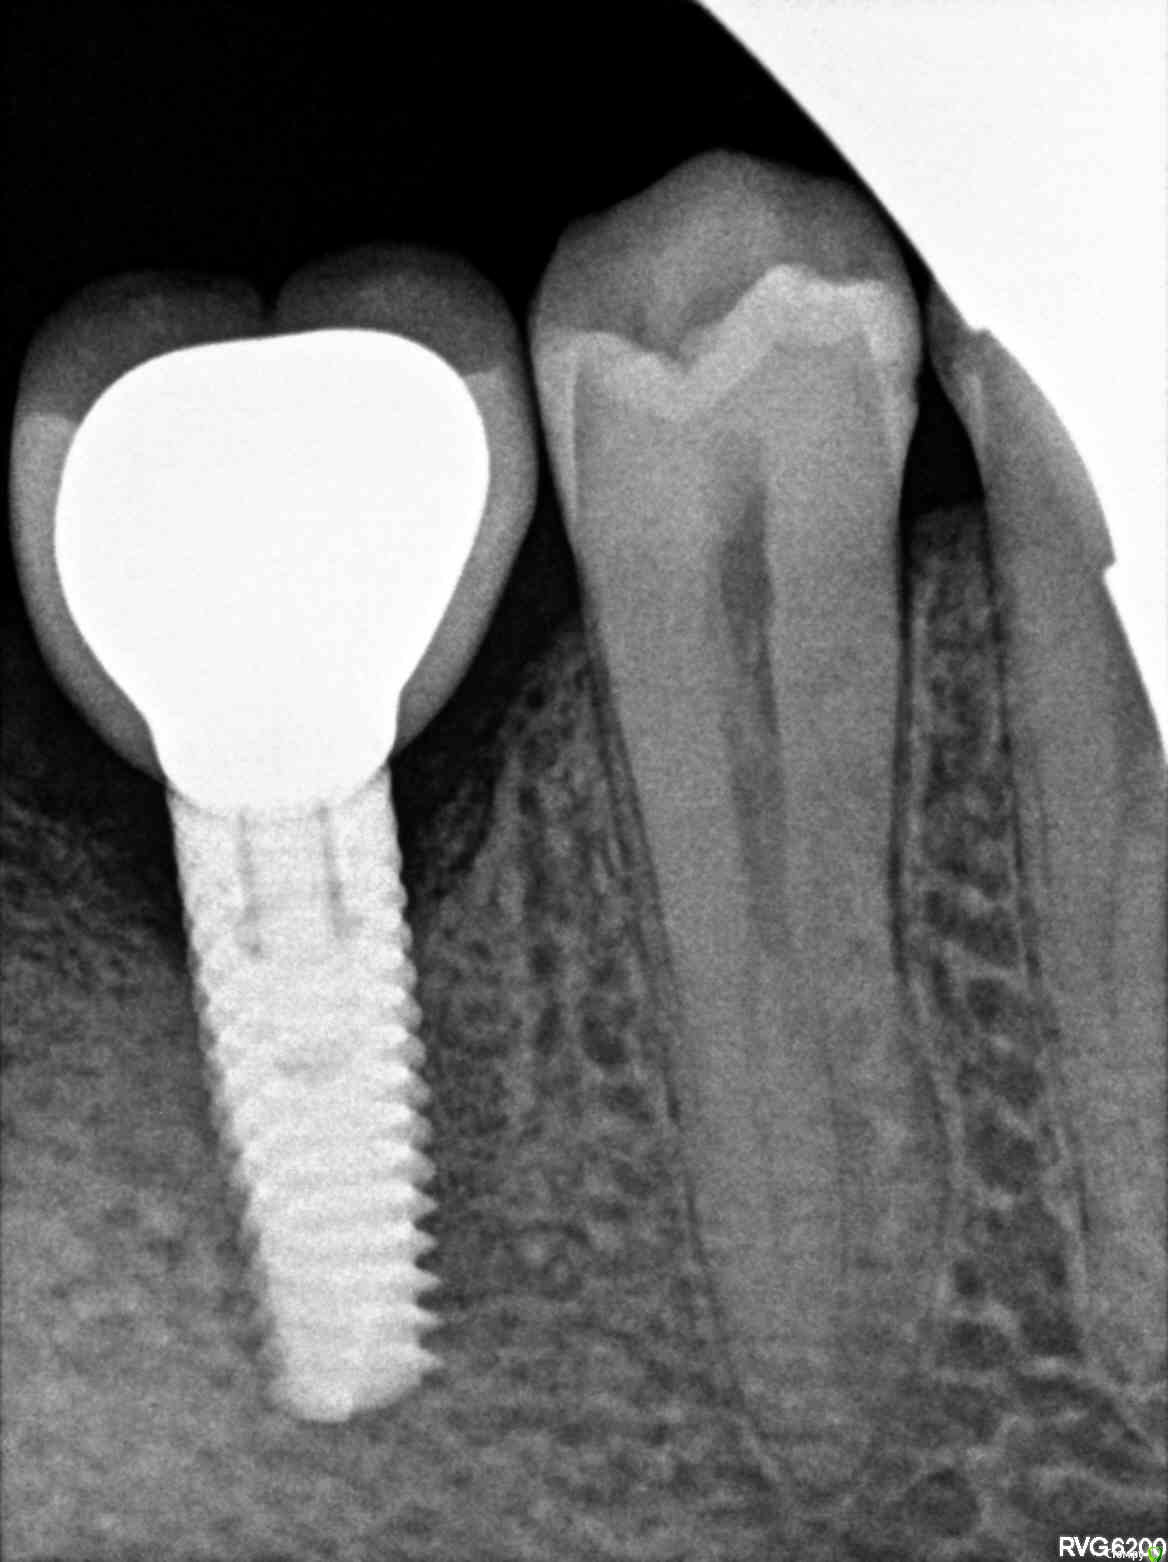

freeman22 Опубликовано 18 декабря, 2017 Поделиться Опубликовано 18 декабря, 2017 Здравствуйте. Что можете сказать по данному импланту и установленной на него коронкой? 6 нижний зуб. Ссылка на комментарий

freeman22 Опубликовано 18 декабря, 2017 Автор Поделиться Опубликовано 18 декабря, 2017 (изменено) Установка импланта прошла нормально, когда отошла анестезия вообще ничего не болело (на удивление), хотя уже приготовил Кетанов)) И вообще меня имплант никак не беспокоил, но спустя 3 месяца появилась ноющая, даже какая-та тянущаяся боль отдающая на передние зубы (точнее даже скорее на один из передних зубов), потом добавилась резкая пульсирующая боль, но она не долгая и иногда бывает. В основном какая-то словно тянущая передний зуб боль. Я спустя 3 месяца, когда появилась эта боль (ещё без коронки на имплант) показывал имплант имплантологу, который его ставил, но он лишь обнаружил значительное рассасывание (убывание) кости причём его удивляло, что сама соединительная ткань чистая без фиброзной ткани, но почему-то не происходит интеграция соединительной ткани ещё с какой-то, там что-то добавлял (возможно костную ткань), но кость всё равно убывает на этом снимке это отчётливо видно.Насколько я понимаю имплант остеоинтегрирован и с ним всё в порядке. Собственно вопрос может ли данный имплант давать такие боли (спустя несколько месяцев после установки, до этого нормально всё было) или это скорее всего другие жевательные зубы (с живыми, не удалёнными нервами) так отдают на передний зуб(ы) боль.Ещё до установки импланта на соседнем 7 зубе лечил пришеечный кариес (был сбоку и близко к десне) и стал виден, после удаления зуба. После лечения спустя сутки появилась реакция зуба на холодные раздражители и потом была такая боль, как я описал выше. Где-то спустя 3-4 недели всё прошло. Опять же ходил к тому терапевту который лечил кариес, он сказал, что там был лёгкий кариес, ну максимум средний и таких болей быть не должно...Вот снимки 7 зуба после лечения кариеса. Изменено 18 декабря, 2017 пользователем freeman22 Ссылка на комментарий

Irouil Опубликовано 18 декабря, 2017 Поделиться Опубликовано 18 декабря, 2017 (изменено) Костная резорбция есть, она не криминальная, можно закрыть мягкотканной пластикой (десны пришить немного). Надо ещё фото в полости рта, возможно именно это Вам и сделали. Болит, по моему мнению, что-то ещё. Может следующий зуб. Надо проверить витальность зубов на этой половине нижней челюсти. Главный подозреваемый - следующий зуб (4.7), там хронический пульпит судя по всему. Также не стоит исключать неврологию, но это если в полости рта ничего не найдете. Альфа био? Ставили одномоментно?Там разве не намек на конус? Изменено 18 декабря, 2017 пользователем Irouil Ссылка на комментарий

колесников Опубликовано 18 декабря, 2017 Поделиться Опубликовано 18 декабря, 2017 У вашего импланта проблема локальная,таких болей он не может давать. Где то пульпитный зуб. Ссылка на комментарий